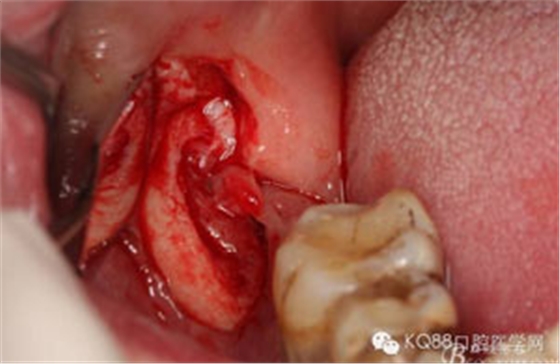

圖6.行角形瓣切開、翻瓣、暴露骨面,可見48牙冠表面有炎性肉芽組織